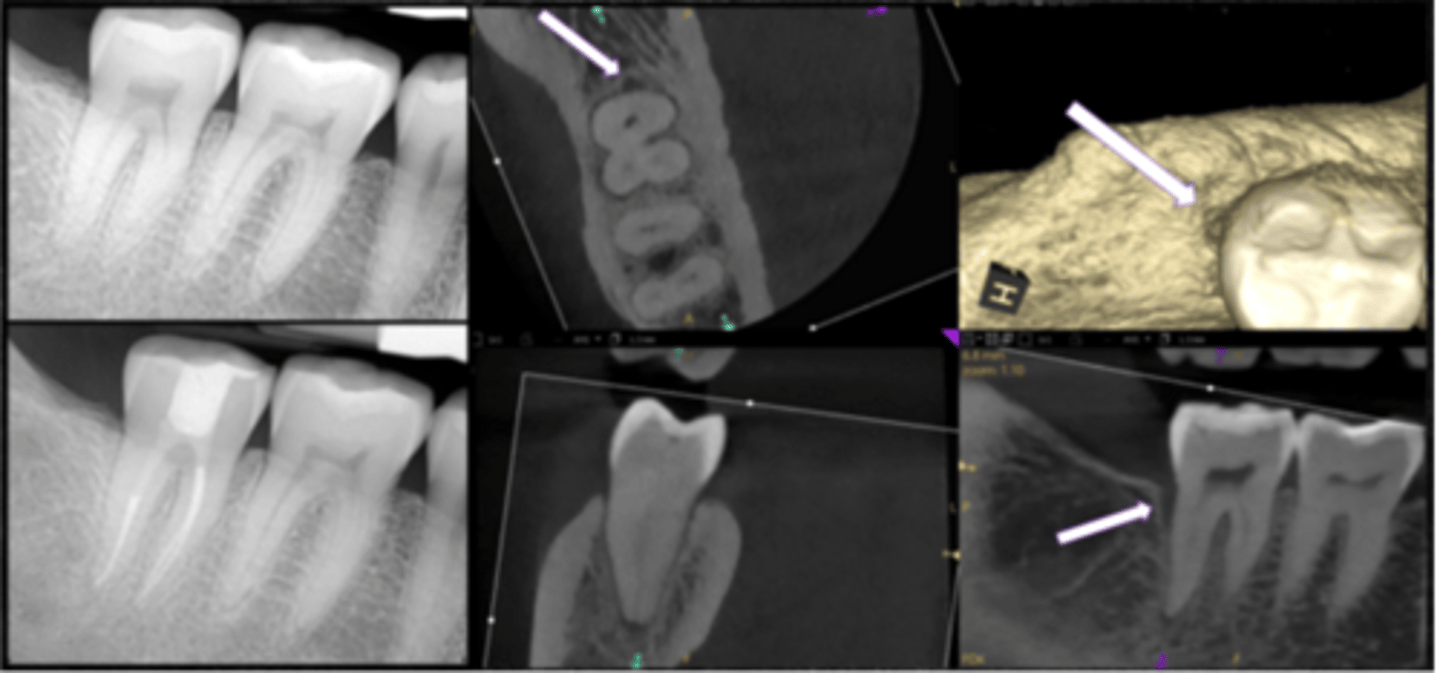

What type of lesion?

- Tooth #31 with shallow restoration. Crack developed extending through distal marginal ridge and onto distal surface

- Isolated, narrow area of bone loss develops adjacent to crack (see white arrows)

- Pulpal dx: pulp necrosis; Periapical dx: symptomatic apical periodontitis

- Recent study showed favorable longterm prognosis in cracked teeth after RCT, deep intraorifice barriers, occlusal adjustment, and immediate crown

Cracked teeth